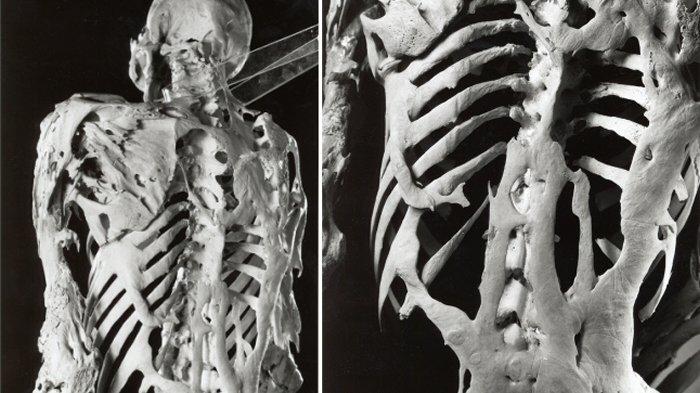

Erken teşhis önem arz etmektedir. Doğuştan deforme hale gelmiş ayak başparmağının varlığı ise belirti niteliğindedir. Bu belirtiye sahip kişiler öncelikle kemik taraması, röntgen, genetik testlerini vb. yaptırması gerekir.

- Eklemlerin kısıtlı hareketleri, genellikle ilk başlarda boyun ve omuzlar.

- Anormal derecede kemik büyümesinin vücut şeklinize yansıması.